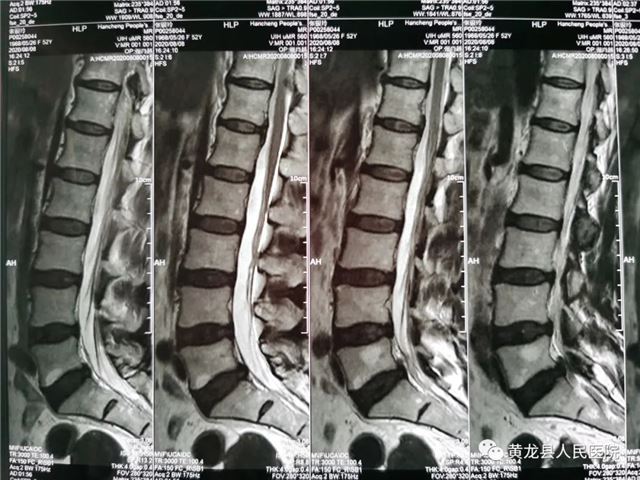

张某,女,52岁,近1月来,出现腰部疼痛,反复发作,并向左侧下肢放射,劳累后加重,休息后减轻,无法正常行走,严重影响生活质量,在家人陪同下来到黄龙县人民医院外科就诊。恰逢唐都医院骨科帮扶支援专家高全有副主任医师门诊坐诊,首诊详细了解患者病史,经仔细查体,结合影像学检查,最终诊断为:腰椎间盘突出症(L5-S1)。

术前腰椎MRI